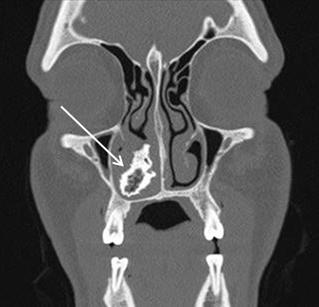

Jacqueline K. Le, MD, Decision Editor Desert Regional Medical Center

Christopher San Miguel, MD, Decision Editor Ohio State Univesity Wexner Medical Center

Robert Suter, DO, MHA UT Southwestern Medical Center

Khrongwong Musikatavorn, MD King Chulalongkorn Memorial Hospital, Chulalongkorn University, Bangkok, Thailand

Leslie Zun, MD, MBA Chicago Medical School

Linda S. Murphy, MLIS University of California, Irvine School of Medicine Librarian

Nadeem Qureshi, MD St. Louis University, USA

Emirates Society of Emergency Medicine, United Arab Emirates

Niels K. Rathlev, MD Tufts University School of Medicine

Pablo Aguilera Fuenzalida, MD Pontificia Universidad Catolica de Chile, Región Metropolitana, Chile